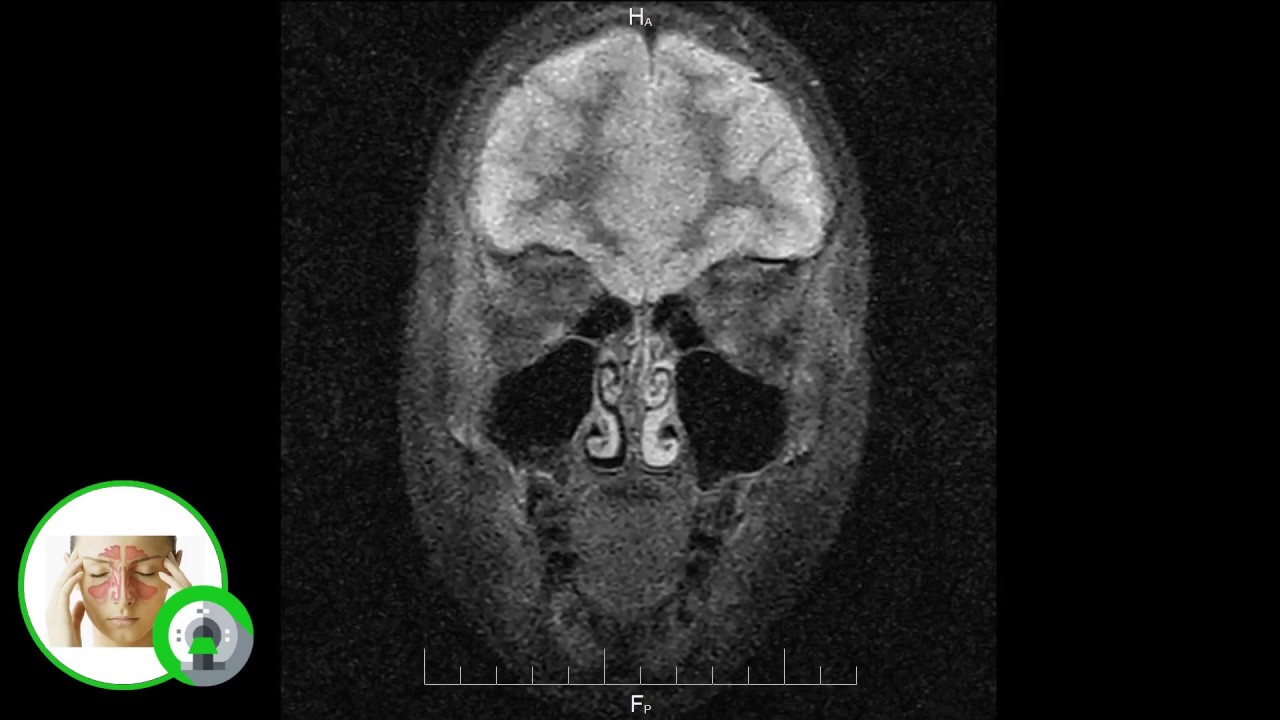

Типичное мукоцеле лобной пазухи. При исследовании в режиме подавления сигнала от жидкости выявляется объемное образование с округлым выпячиванием костной стенки пазухи со смещением глазного яблока вниз.

Что покажут снимки МРТ околоносовых пазух при мукоцеле

- Округлое образование с высокой интенсивностью сигнала на Т2-взвешен- ном изображении

- Сгущение секрета приводит к обратным показателям интенсивности сигнала (низкая интенсивность сигнала на Т2-взвешенном изображении, высокая — на Т1 -взвешенном изображении)

- В отличие от медленно растущих опухолей не усиливается после введения гадолиния.